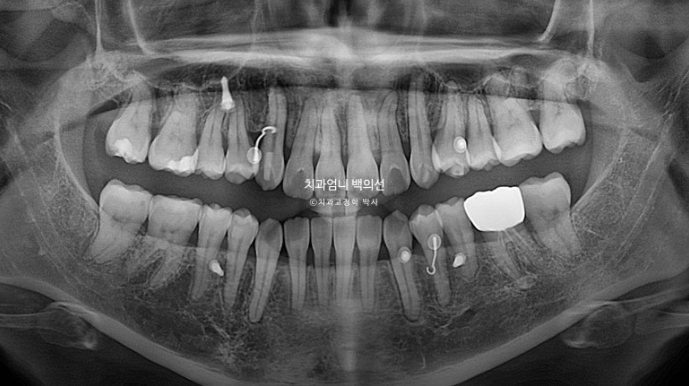

24.11

재제작 들어갈 당시 파노라마 엑스레이입니다.

치근흡수는 없고 치근평행도는 양호합니다.

재제작시 앞니에 치축 개선을 더했기 때문에 치료가 완전히 끝난 후 엑스레이에서는 치근평행도가 더 개선되었을 것입니다.